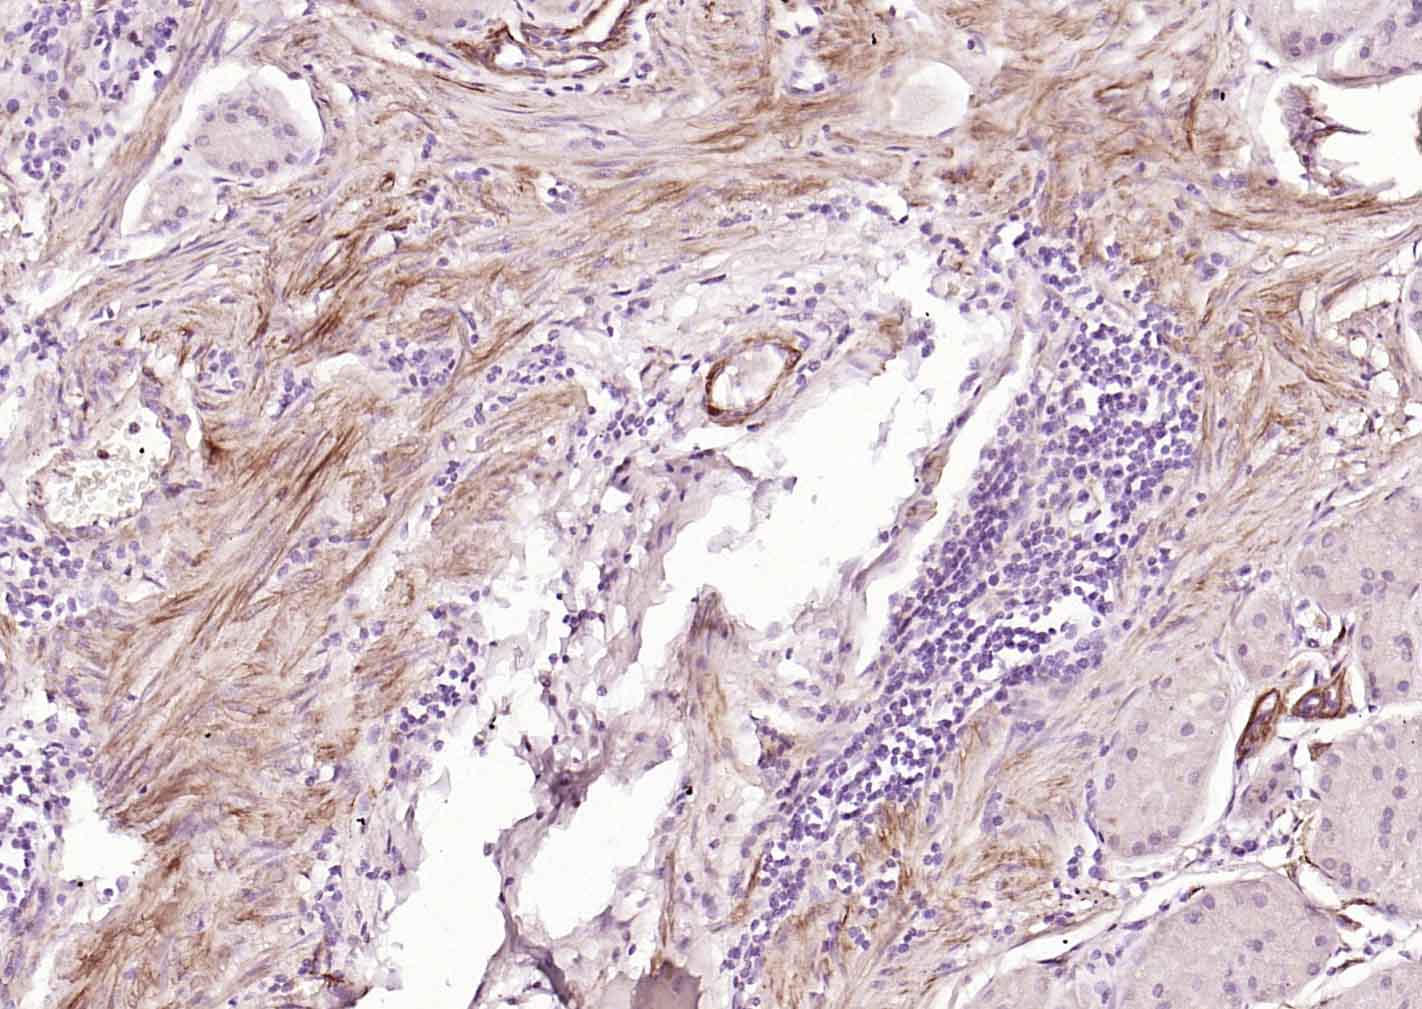

產(chǎn)品圖片

Paraformaldehyde-fixed, paraffin embedded (human stomach); Antigen retrieval by boiling in sodium citrate buffer (pH6.0) for 15min; Block endogenous peroxidase by 3% hydrogen peroxide for 20 minutes; Blocking buffer (normal goat serum) at 37°C for 30min; Incubation with (Caldesmon/CDM) Monoclonal Antibody, Unconjugated (bsm-60918R) at 1:200 overnight at 4°C, followed by operating according to SP Kit(Rabbit) (sp-0023) instructionsand DAB staining.